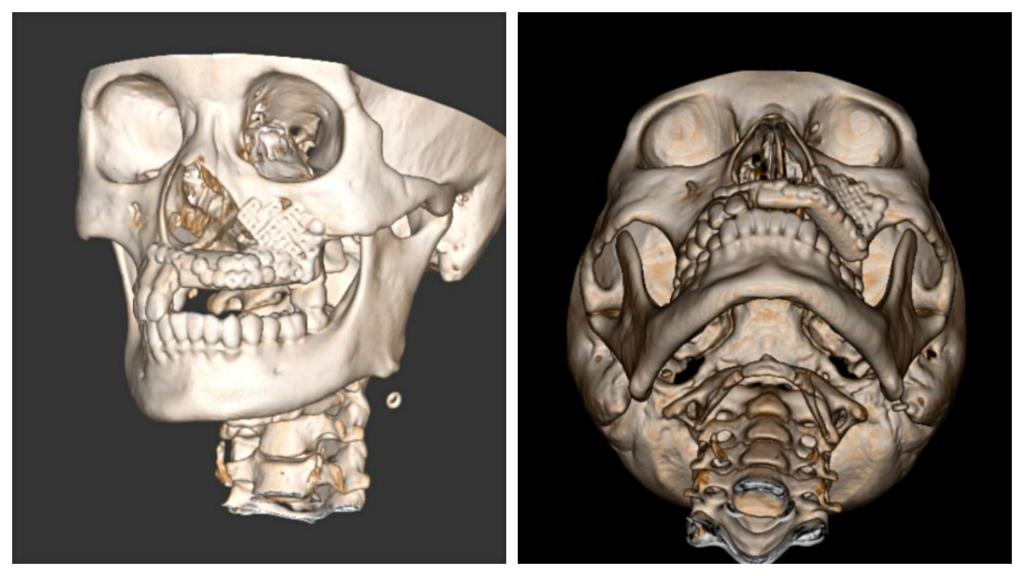

本次手术历时6个小时,吴亚东团队精确切除了患者左上颌骨肿瘤,利用数字化血管化腓骨瓣及个性化钛网重新恢复了这位年轻妈妈的面型及上颌骨缺损。术后在口腔颌面外科护理团队的精心护理下,患者病情恢复良好,现已治愈出院。面型基本对称,移植的腓骨瓣存活良好。半年后,这位年轻的妈妈就可以利用“新的上颌牙槽嵴”进行种植牙恢复咀嚼功能。

手术的成功标志着beat365正版唯一官网必一附属口腔医院口腔颌面外科修复重建技术已经可以涉及头颈颌面部各区域各类软硬组织缺损,填补了省内上颌骨缺损修复重建的技术空缺。